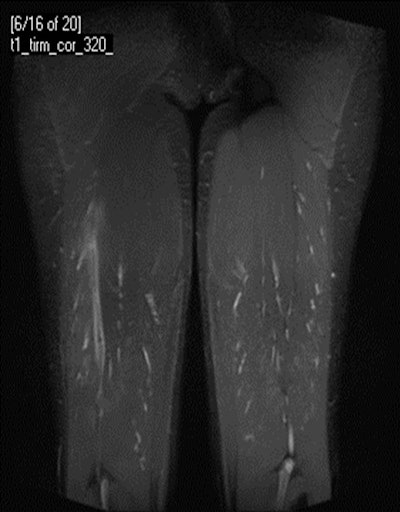

A 24-year-old male professional football player who presented with sudden onset of pain following striking of the ball. Coronal STIR MRI demonstrates focal defect within the left rectus femoris central muscle at the musculotendinous junction (grade II strain). Note the feathery edema pattern within the muscle radiating from the primary injury site.A 24-year-old male professional football player who presented with sudden onset of pain following striking of the ball. Coronal STIR MRI demonstrates focal defect within the left rectus femoris central muscle at the musculotendinous junction (grade II strain). Note the feathery edema pattern within the muscle radiating from the primary injury site. Extended field-of-view ultrasound demonstrates loculated hematoma at the musculotendinous junction with surrounding increased reflectivity within the rectus femoris muscle. Images courtesy of Dr. Justin Lee, Chelsea and Westminster Hospital, London.Extended field-of-view ultrasound demonstrates loculated hematoma at the musculotendinous junction with surrounding increased reflectivity within the rectus femoris muscle. Images courtesy of Dr. Justin Lee, Chelsea and Westminster Hospital, London.